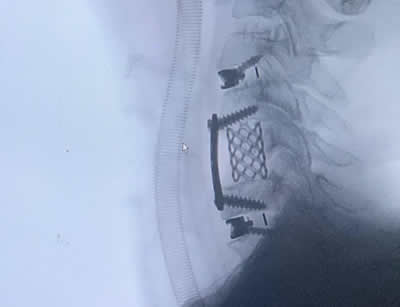

GALLERY

Images gallery